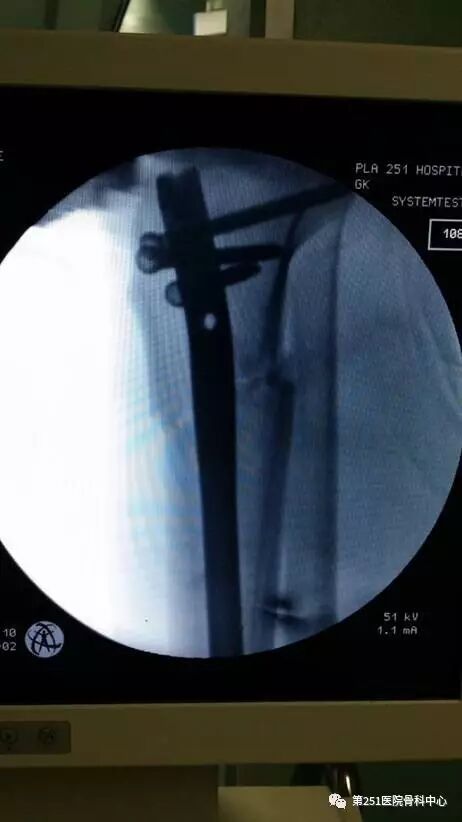

病例6:男性,39岁,车祸伤SchatzkerⅥ型胫骨平台骨折。

![]()